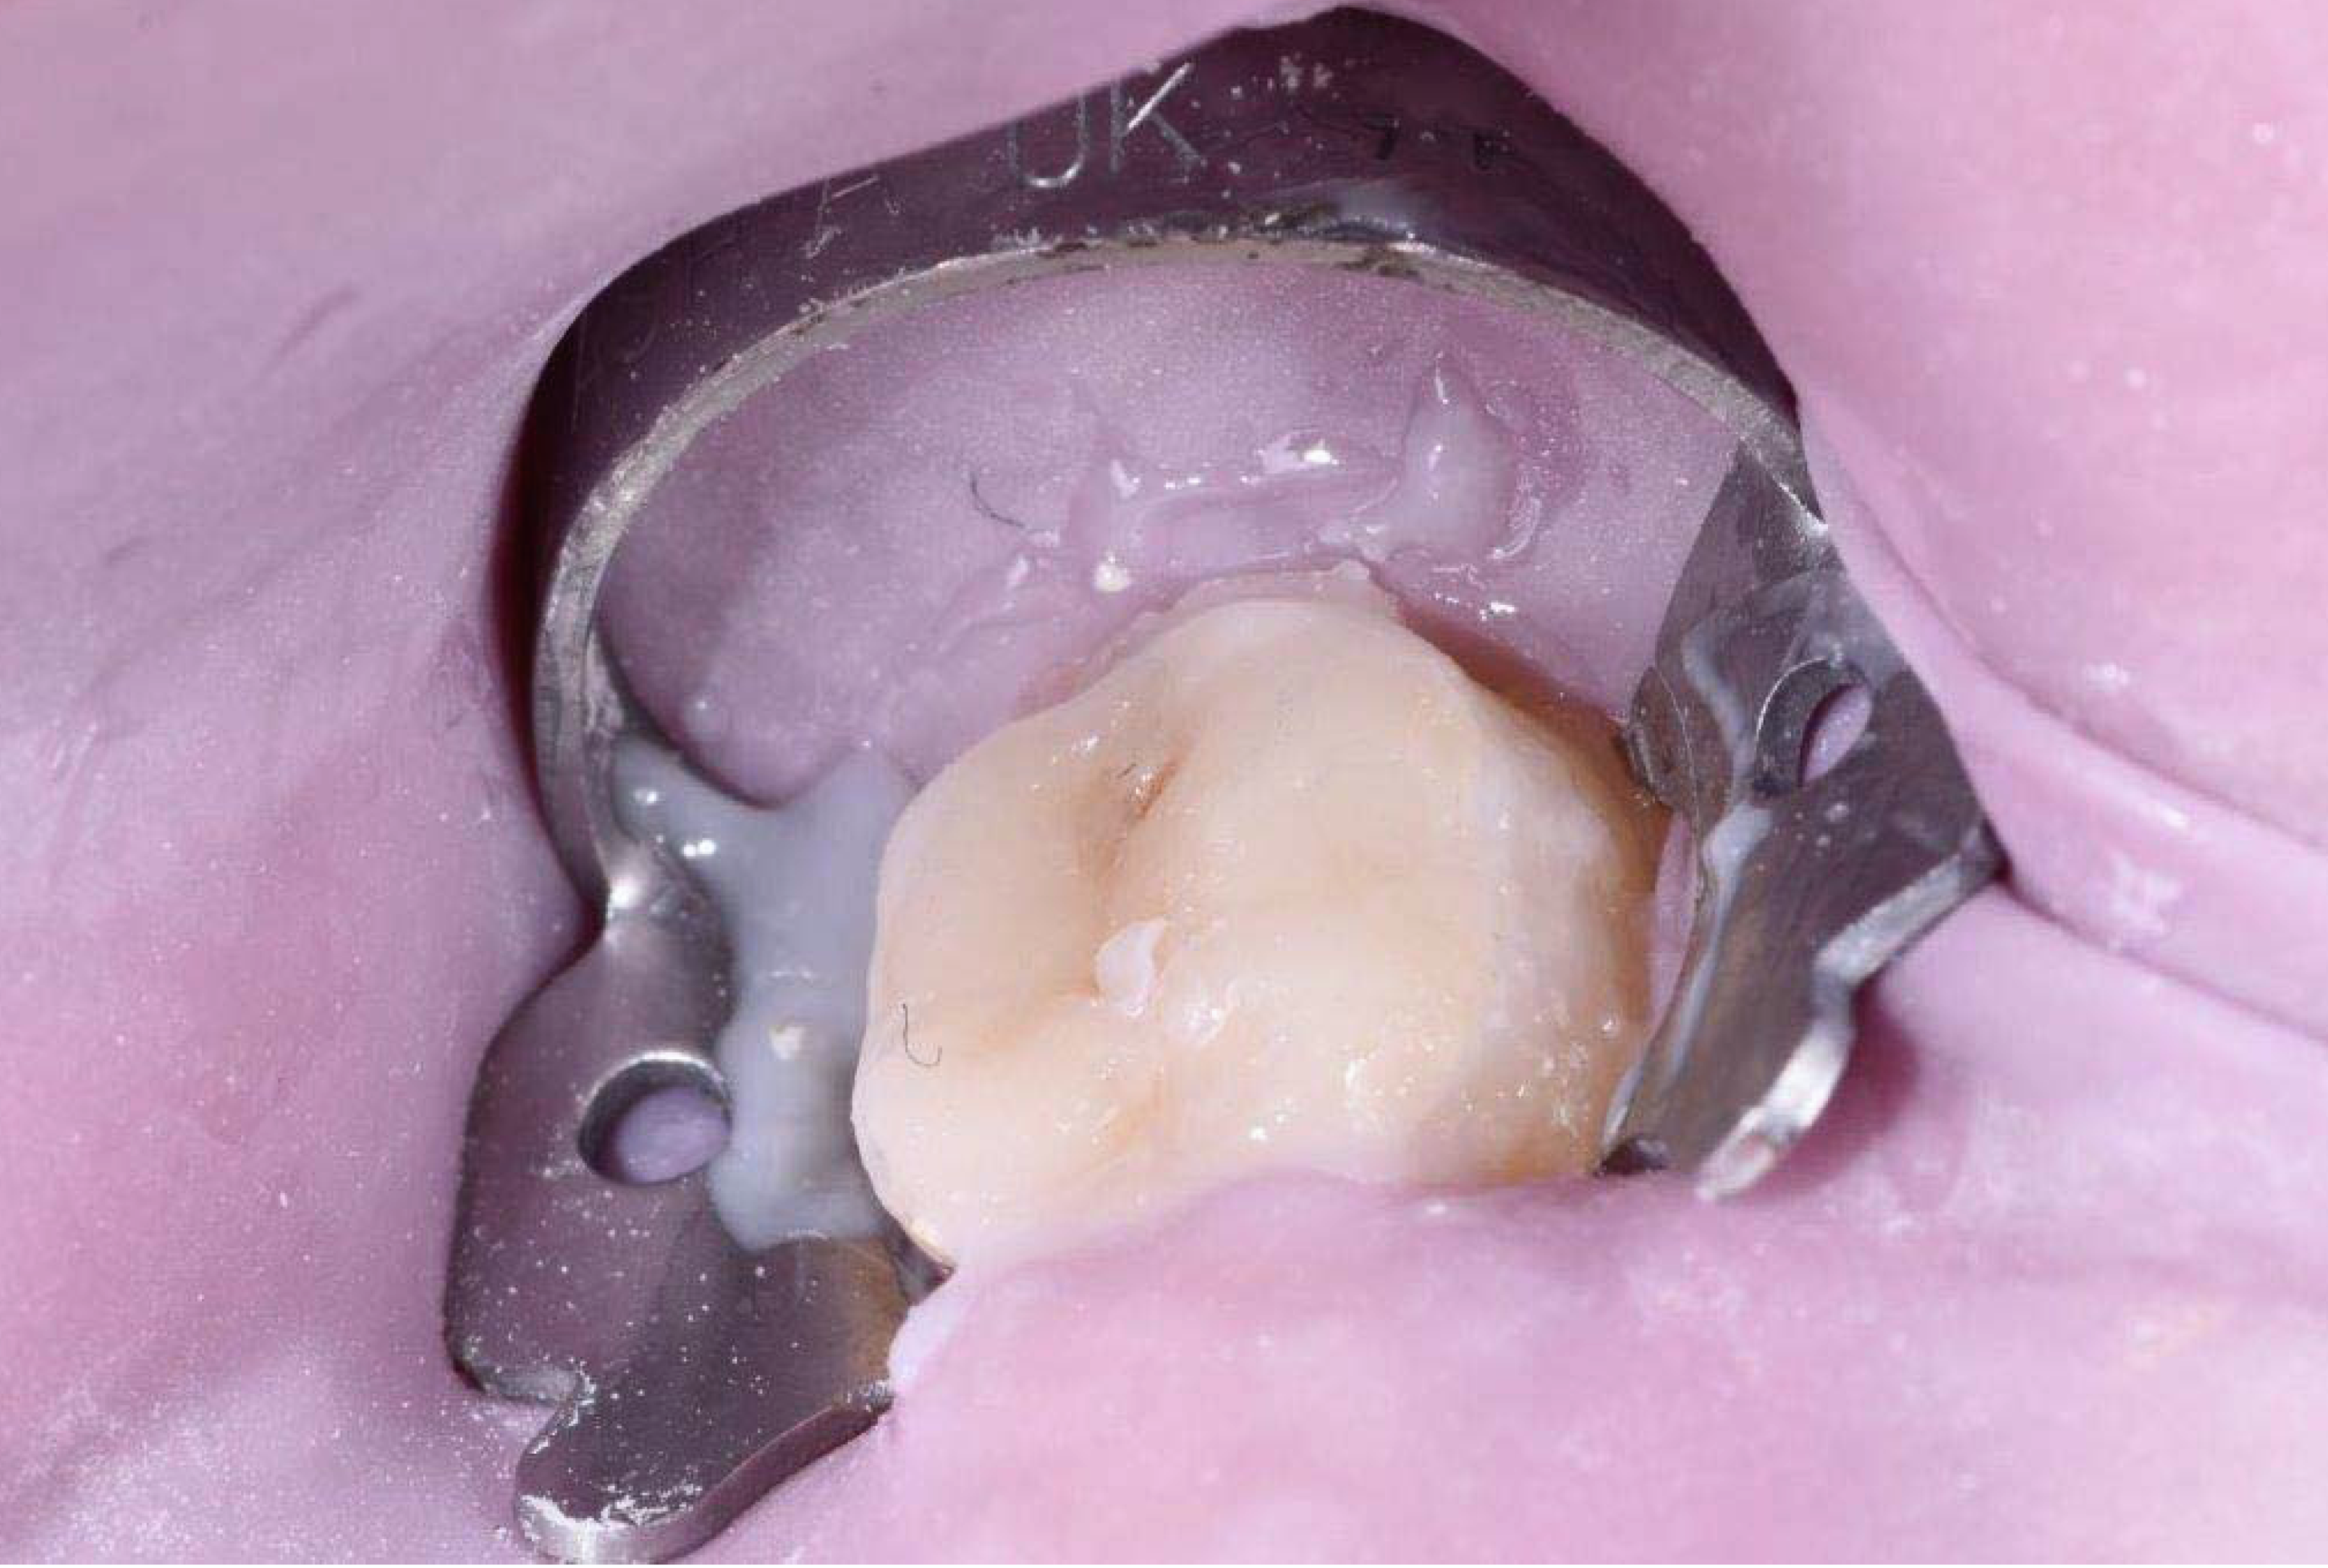

2.2. Clinical Case